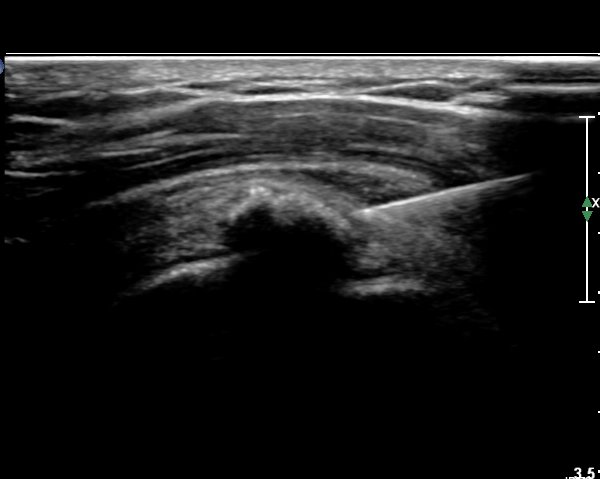

±Ø»ó°Ç Á¾´Ü¸é °Ë»ç»ó¿¡¼­ Á¡¾×³¶³»¿¡ ÁÖ»ç¹Ù´ÃÀÌ À§Ä¡ÇÑ °ÍÀÌ º¸ÀδÙ(»çÁø 3).

Á¡¾×³¶³» ÁÖ»ç ÈÄ ÁÖ»ç¹Ù´ÃÀ» ¹Ýº¹ÀûÀ¸·Î ´õ ÁøÀÔ½ÃÄÑ ¼®È¸¸¦ ºÐ¼âÇÑ´Ù(»çÁø 4).